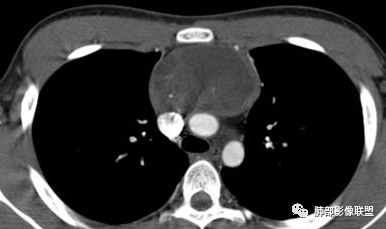

水晶石头:患者老年男性,发现皮肤粘膜黄染5天,右肺占位1天。

胸部CT:右肺中叶内侧段紧邻心脏实性结节,边缘光滑,边界清楚,宽基底与胸膜相连,内可见不规则钙化,钙化内见点状低密度影,增强中度强化,综合考虑良性病变。畸胎瘤可能大,鉴别胸膜孤立性纤维瘤及胸腺瘤。

王秀仙:右侧前纵隔肿块,边缘分叶,周围肺组织推移,宽基底与纵隔胸膜相连,可见胸膜尾征,密度不均,病灶中心可见斑块状钙化,右侧内乳动脉位于病灶前外侧并略增粗,实性成分明显强化,考虑纵隔畸胎瘤,鉴别胸腺瘤。